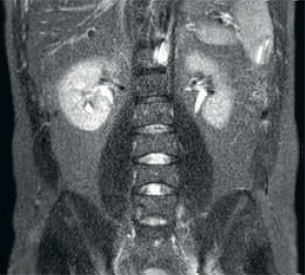

Resultado: imágenes ruidosas que usan parámetros de exploración idénticos

Mayor consistencia y mejor calidad de imagen La tecnología de recepción de RF dStream digitaliza la señal del resonador magnético directamente en la bobina de radiofrecuencia, lo que resulta en un aumento de hasta un 40 % más de la SNR* en todo el volumen de la imagen. Flujo de trabajo simplificado y rendimiento mejorado La bobina posterior integrada en la mesa elimina el manejo de la bobina en el 60 % de los exámenes. Las ligeras bobinas anteriores conformadas y las conexiones de bobina de un solo cable y de una sola mano contribuyen a la facilidad operativa.